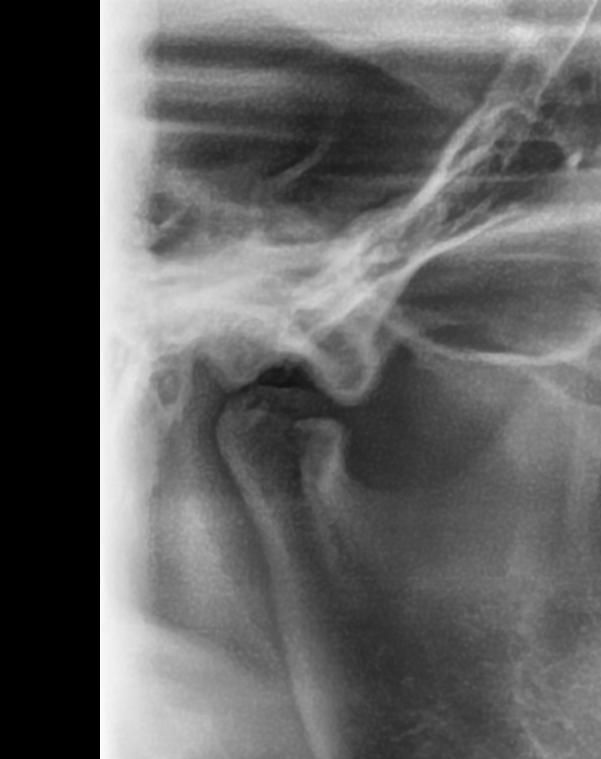

턱 관절 과두 상태 전 후 상태 한 번 봐주세요

최근에 턱 관절 통증 때문에 사진을 한 번 찍어 봤는데요 예전 사진과 비교 했을 때 어떤지 한 번 봐주시겠어요?

어떤 문제가 있는지 상세히 알려주시면 감사하겠습니다

사진1,2가 전이고 3,4가 후 입니다

• 3번 째 사진

엑스레이 상으로도 턱관절이 좋아 보이진 않습니다. 일단 구강내과를 가셔서 턱관절 정밀검사를 받아보시고 치료를 받으시는게 좋을것같습니다.

파노라마 사진으로는 턱관절을 정확하게 진단하기는 어렵습니다. 과두부분이 평평하게 되어있는 모양으로 유추해 봤을때 과두에 강한힘이 오래동안 작용했을수 있습니다. 턱관절질환은 턱관절에 가해지는 힘이 강해서 생기기 때문에 턱관절에 가해지는 힘을 줄이는것이 좋습니다.